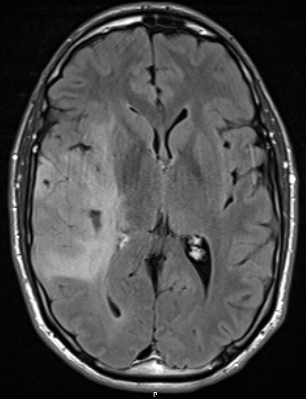

During follow up, possible progression on the left side in the MRI around the posterior ventricle.

1748327265233.png

FET-PET confirms it